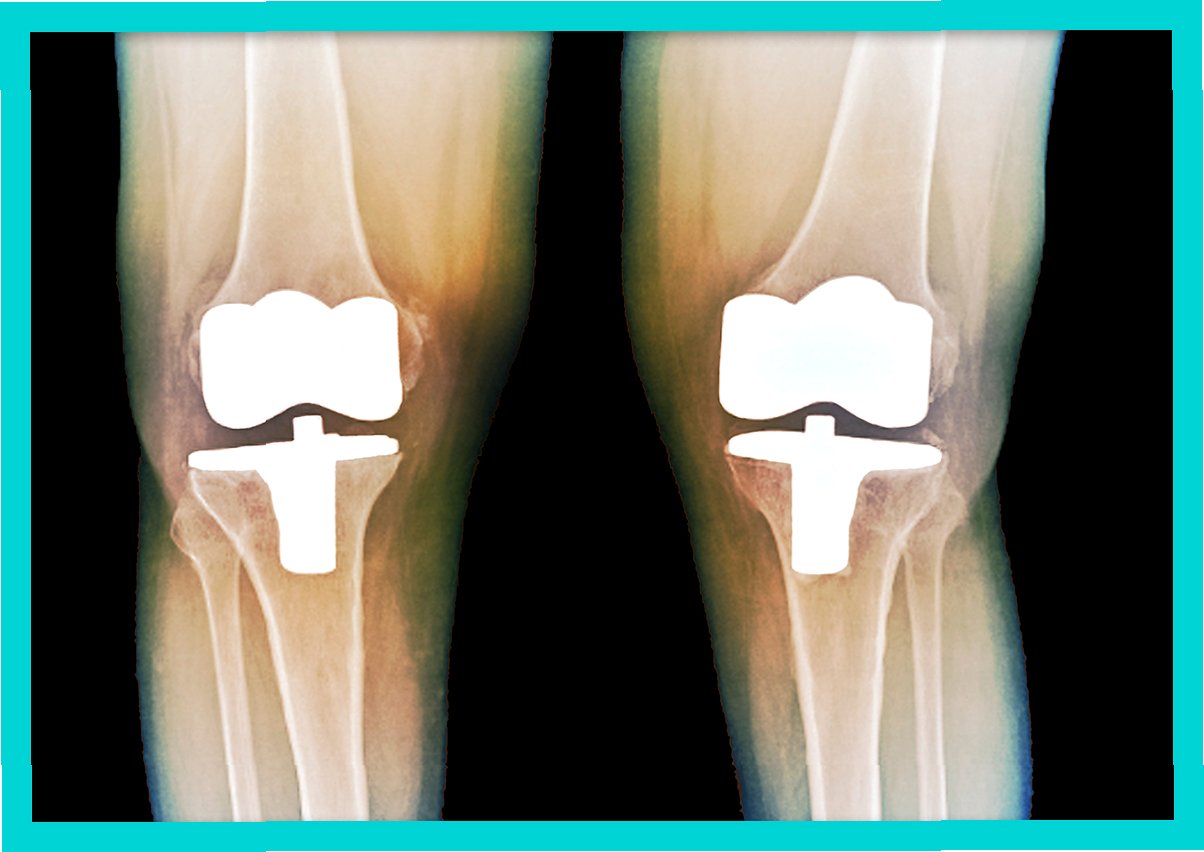

인공 관절 수술: 손상된 무릎을 대체하는 혁신적인 치료법

인공 관절 수술은 심하게 손상된 무릎 관절을 인공 관절로 대체하는 수술입니다. 주로 퇴행성 관절염, 류마티스 관절염 등, 연골 손상이 심하고 보존적 치료에 효과가 없는 경우에 시행됩니다. 인공 관절은 금속과 플라스틱으로 만들어지며, 환자의 무릎에 맞춰 맞춤 제작됩니다. 수술 후에는 통증 감소, 관절 기능 회복, 활동 범위 증가 등의 효과를 기대할 수 있습니다. 수술 방법은 크게 전치환술과 부분 치환술로 나뉘며, 환자의 상태에 따라 적합한 방법을 선택합니다. 인공 관절 수술은 오랜 기간 동안 많은 환자들의 삶의 질을 향상시켜 온 효과적인 치료법입니다.